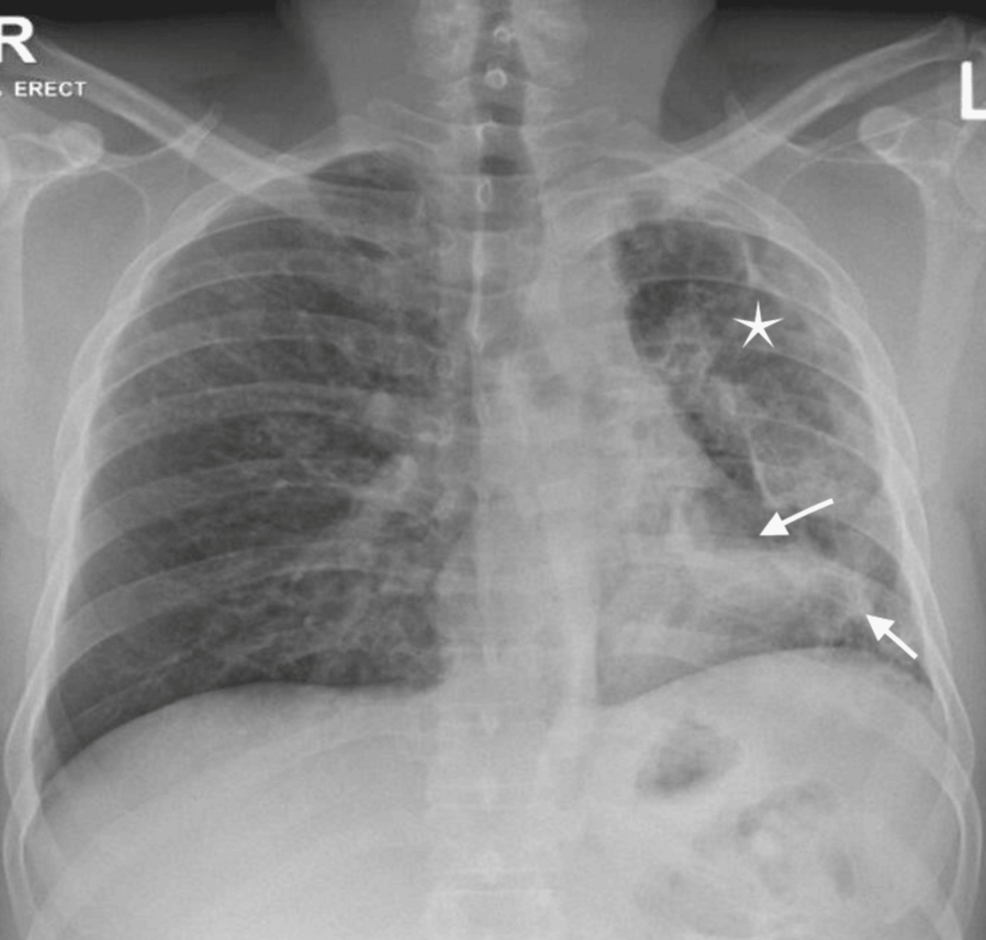

The case report, published in the Cureus Journal of Medical Science, underscores the diagnostic challenges presented when patients exhibit symptoms of both BCCPA and MOTT infection. Both conditions can cause similar symptoms – chronic cough, fatigue, weight loss, and cavitary lesions in the lungs – leading to potential delays in accurate diagnosis and appropriate treatment. **BCCPA**, a serious fungal infection typically affecting individuals with underlying lung disease, is often misdiagnosed as tuberculosis. Simultaneously, MOTT infections, while not as contagious as tuberculosis, are becoming more prevalent, particularly in individuals with structural lung abnormalities.

BCCPA stands for Bilateral Chronic Cavitary Pulmonary Aspergillosis. It’s a serious fungal infection of the lungs, often occurring in individuals with pre-existing lung disease. It causes cavities to form in the lungs and can lead to chronic symptoms like cough, fatigue, and weight loss.